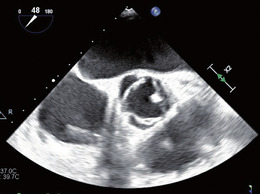

Abb. 1 Aortenklappe ohne flottierende Vege- tation. Unspezifische, rundliche Verdickung des Klappenrandes